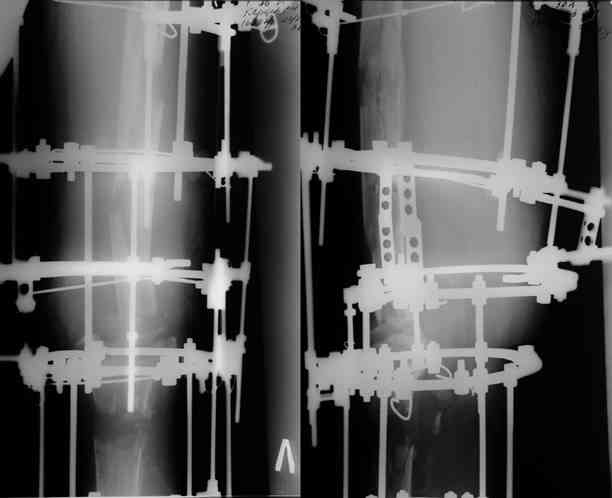

Этот стиль мне полностью приемлем и понятен. Наверно я бы поступил также. Но статистика упрямая вещь. Сколько у тебя или у другого врача опыта по замещению дефектов бедра? У меня за 25 лет работы 3, и еще около 15 случаев удлинения бедра. Случай у тебя очень сложный. Если Вы выбираете Илизаровскую методику то надо на в/з хорошую дугу, не менее 4-5 спиц с напайками.Стержни хороши когда кость не измучена и на 2-4 месяца. Здесь аппарат на 6-8 месяцев. Если есть желание я только за, и

желаю только успеха и чтоб все трудности которые будут преодолел.

Прикрепляю пример замещения дефекта бедра 20 см, после резекции по поводу опухоли, эндопротеза Сиваша, вялотекущего остеомиелита со свищами в течении 3 лет. Получилось хорошо и всего за 6 месяцев в аппарате. Колена не было. У Вас случай сложнее. Это было в 1998г. Я работал в ЦИТО и у меня было 4 больных, я занимался им с утра до ночи. Сейчас 60 больных и операций в нашем отделении 25-30 в неделю.Если могу чем помочь - нет проблем.